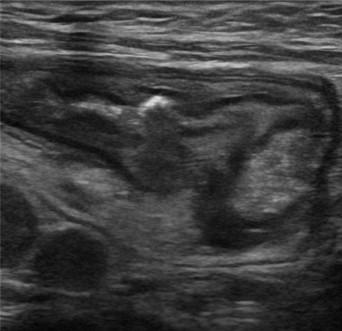

Viêm ruột

» Thông tin: Nữ giới – 55 tuổi.

» Lâm sàng: Tiêu chảy.